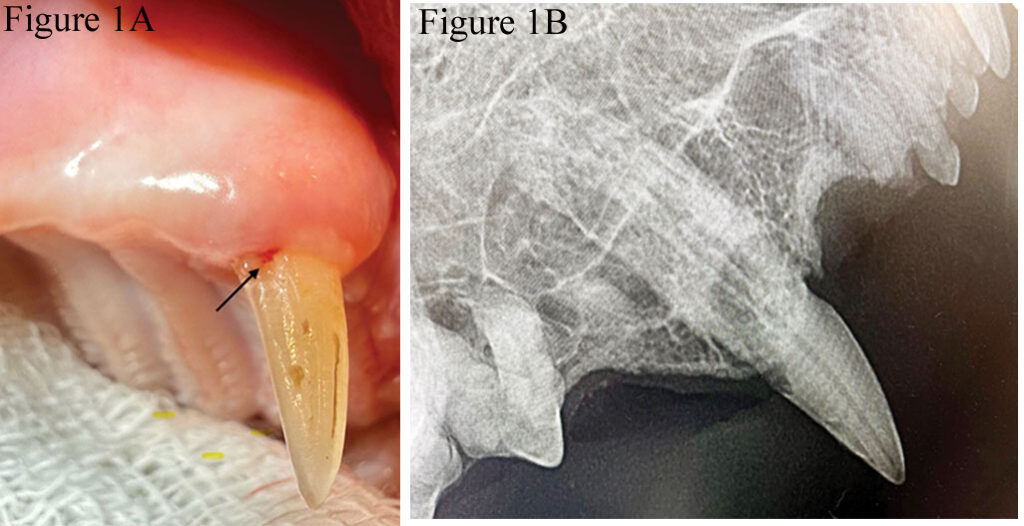

A student named Meredith, who went through the dentistry rotation when I was a professor at Penn, once stated, “It seems gingiva is the ‘omentum of the mouth,’” which I felt was a very thoughtful metaphor. Gingiva fills the resorption defect and covers a portion of the cervical crown. Even under anesthesia, lightly running an explorer along the gingival margin may detect an area of resorption, resulting in the tip of the explorer “catching” in the defect and a quiver or chatter of the lower jaw (Figure 1). When tooth resorption reaches the crown and results in exposed dentinal tubules, discomfort occurs when fluids, air, or a dental explorer passes across those exposed dentinal tubules, resulting in the jaw-opening reflex.